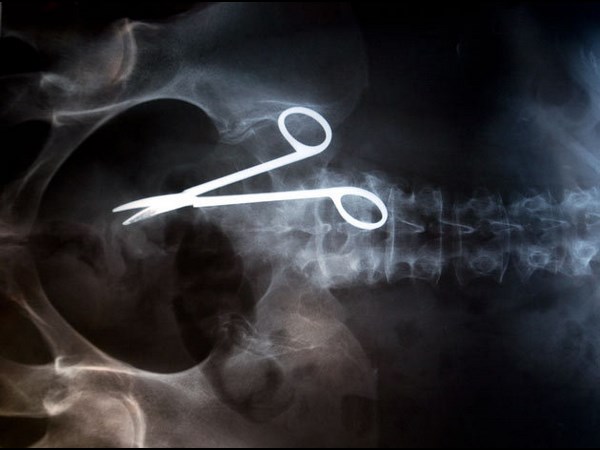

மருத்துவ உலகம் கண்டு வியந்த எக்ஸ் ரே படங்கள்

வயிற்றில் கத்திரிகோல் உள்ளது.